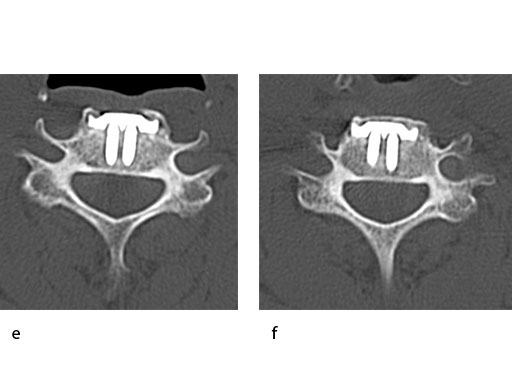

A 51-year-old woman was affected by cervical radiculo-myelopathy due to spinal and neuroforaminal stenosis. The preoperative CT scans are shown at Fig 4 and MRI at Fig 5.

The patient was treated by anterior cervical decompression and fusion (ACDF) with ZERO-P filled with ChronOS. No autologous bone graft was used. Postoperative images are shown (Fig 69).